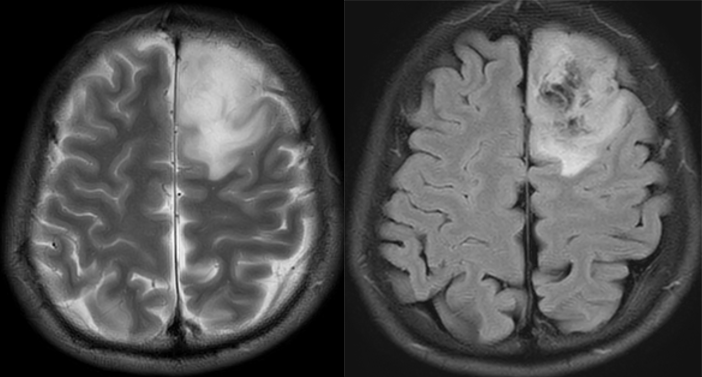

T2WI 看似整体均质高信号,但是 FLAIR 出现明显的低信号(坏死/囊肿),未见强化,不符合 T2-FLAIR 错配。术后为少突胶质细胞瘤 IDH 突变型。

T2WI 看似整体均质高信号,但是 FLAIR 出现明显的低信号(坏死/囊肿),不符合 T2-FLAIR 错配。术后为少突胶质细胞瘤 IDH 突变型。